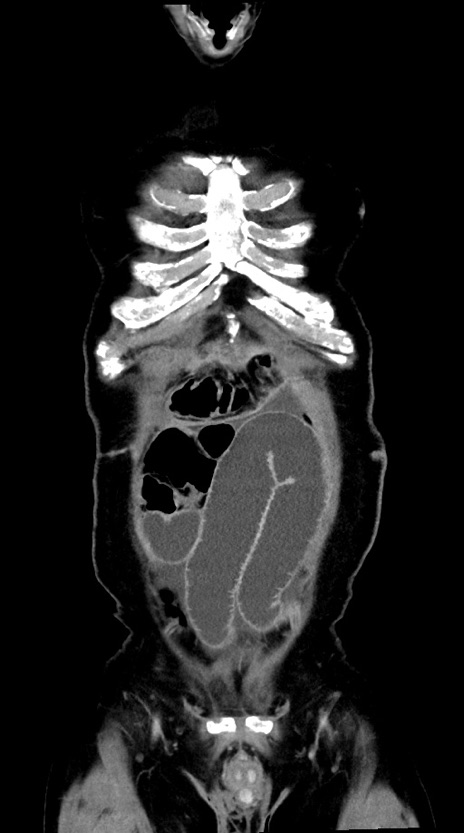

症例28(冠状断像)

【症例】60歳代男性

【主訴】嘔吐

【現病歴】胃癌にて胃全摘後。食思不振が悪化し、夜中に嘔吐することがある。

【既往歴】胃癌、胃全摘、脾摘、胆摘後